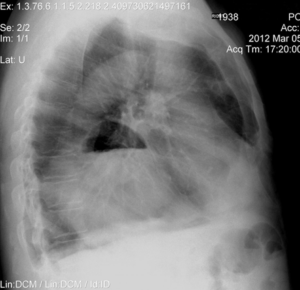

Кардиальная грыжа диафрагмы: рентген признаки

Грыжу диафрагмы на рентген снимке видно. При выполнении боковой рентгенограммы органов грудной клетки округлое низкоинтенсивное затемнение (плюс-тень) визуализируется в переднем реберно-диафрагмальном синусе. При выраженном расширении пищеводного отверстия диафрагмы и выпадении значительной части желудка или кишечника в грудную полость внутри затемнения можно отследить горизонтальный уровень жидкости. Для более качественной верификации рекомендуется контрастирование пищевода барием. Пероральное применение вещества позволяет четко установить размеры, структуру, форму патологического образования. Контрастная эзофагография помогает изучить структуру пищевода, определить сужения, выявить симптом «птичьего клюва» (появляется при опухолевом поражении). Над участком ахалазии прослеживается расширение пищевода, которое хорошо очерчивается контрастом. У пациентов с выраженной ахалазией кардии размер расширения достигает 20 см. При контрастировании барием такое образование имеет подушкообразную форму. В участке выпадения барий задерживается на 2-ое суток.

Чтобы назначить рентгенографию, требуется определение клинических симптомов, позволяющих заподозрить патологию. Назначается диагностика при наличии у пациента определенных клинических признаков: • Гастроэзофагеальные рефлюксы; • Повышение кислотности желудка; • Обострение бронхолегочных болезней; • Сердечнососудистая патология. Рентген органов грудной полости в боковой проекции – образование, подобное на желудок в заднем средостении справа При наличии подозрения грыжу диафрагмы назначаются следующие диагностические методы: 1. Эзофагоскопия (перед рентгенодиагностикой); 2. Биопсия слизистой оболочки желудка; 3. Анализ кала на скрытую кровь; 4. Манометрия эзофагеальная; 5. Импедансометрия; 6. Внутрижелудочная ph-метрия; 7. Рентгенография желудка.

Пример исследований у пациента при подозрении на грыжу пищевода

При выполнении флюорографии органов грудной клетки выявлено полостное образование в области переднего реберно-диафрагмального синуса, которое подобно на кардиофундальный отдел желудка. На рентгенограмме не выявлено инфильтративных теней в проекции легочной ткани. Расширена в поперечнике тень сердца. Заключение: рентгенологически определяется больше данных за грыжу диафрагмы. Рекомендована гастроскопия желудка. После проведения контрастного рентгеноскопического обследования желудка получено заключение: • Не нарушен акт глотания; • Свободная проходимость пищевода; • Расширение участка пищевода с затруднением прохождения бария; • Пищевод переходит в желудок в физиологическом месте; • Желудок фиксирован в кардиофундальном отделе; • Складки ровные, прослеживаются на всем протяжении; • Форма не изменена; • Эвакуация своевременная; • Перистальтика глубокая; • Петли тощей кишки без особенностей. На основе вышеописанных признаков можно предположить кардиофундальную параэзофагеальную грыжу диафрагмы. Фиброгастродуоденоскопия пациенту не проводилась из-за наличия противопоказания – гипертоническая болезнь 3 стадии. Процедура нецелесообразна из-за высокой опасности осложнений.